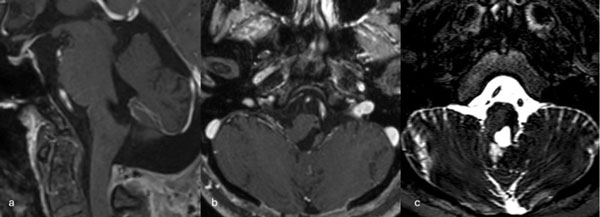

Figura 3. RM preoperatoria de encéfalo. Se evidencia una lesión única intraaxial centrada en puente y pedúnculo cerebeloso derecho, sugerente de un cavernoma roto. A, B y C) Imágenes ponderadas en T2 en cortes sagital, axial y coronal, respectivamente, donde se observa un importante hiperintensidad perilesional, sugerente de edema.

Figura 6. RM preoperatoria de encéfalo. Se evidencia una lesión única intraaxial localizada en el puente y pedúnculo cerebeloso medio izquierdo, hiperintensa en T1 y con un anillo hipointenso en T2, característica de una malformación cavernomatosa con sangrado reciente. A) Imagen ponderada en T1 en corte sagital. B y C) Imágenes ponderadas en T2 en cortes axial y coronal, respectivamente.